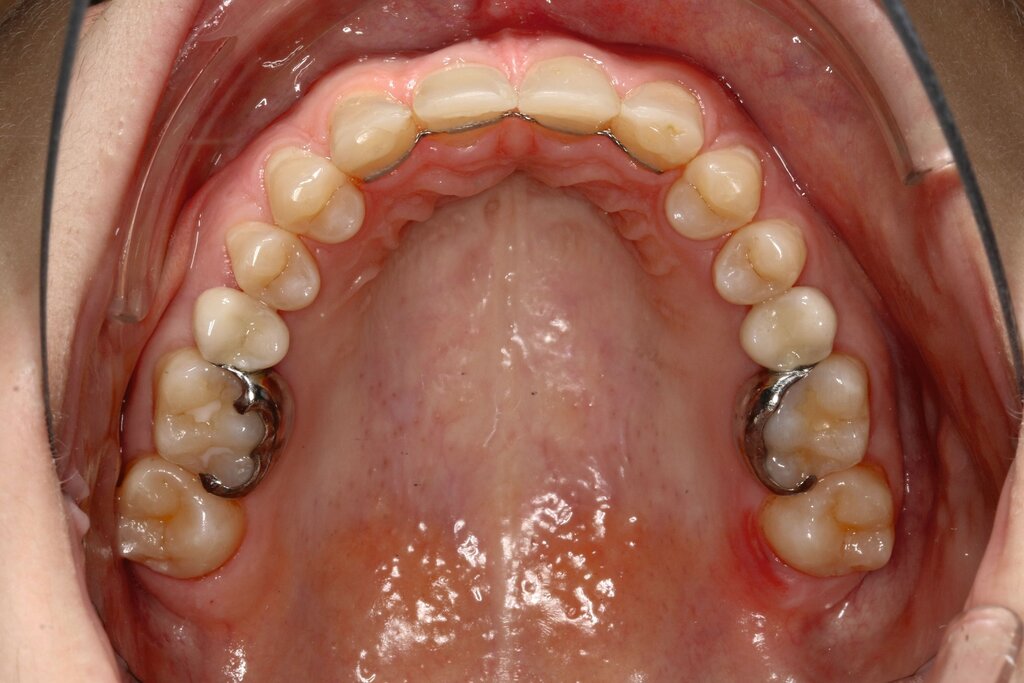

Bei dem gut zwölfjährigen Mädchen sind die seitlichen oberen Schneidezähne (Zähne 12 und 22) nicht angelegt. Zusätzlich zeigten sich verlagerte zweite obere Prämolaren.

b) im Oberkiefer von okklusal nach Mesialisierung von 13, 14 und 15 sowie 23, 24 und 25 und Lückenöffnung außerhalb der ästhetischen Zone mesial 16 und 26